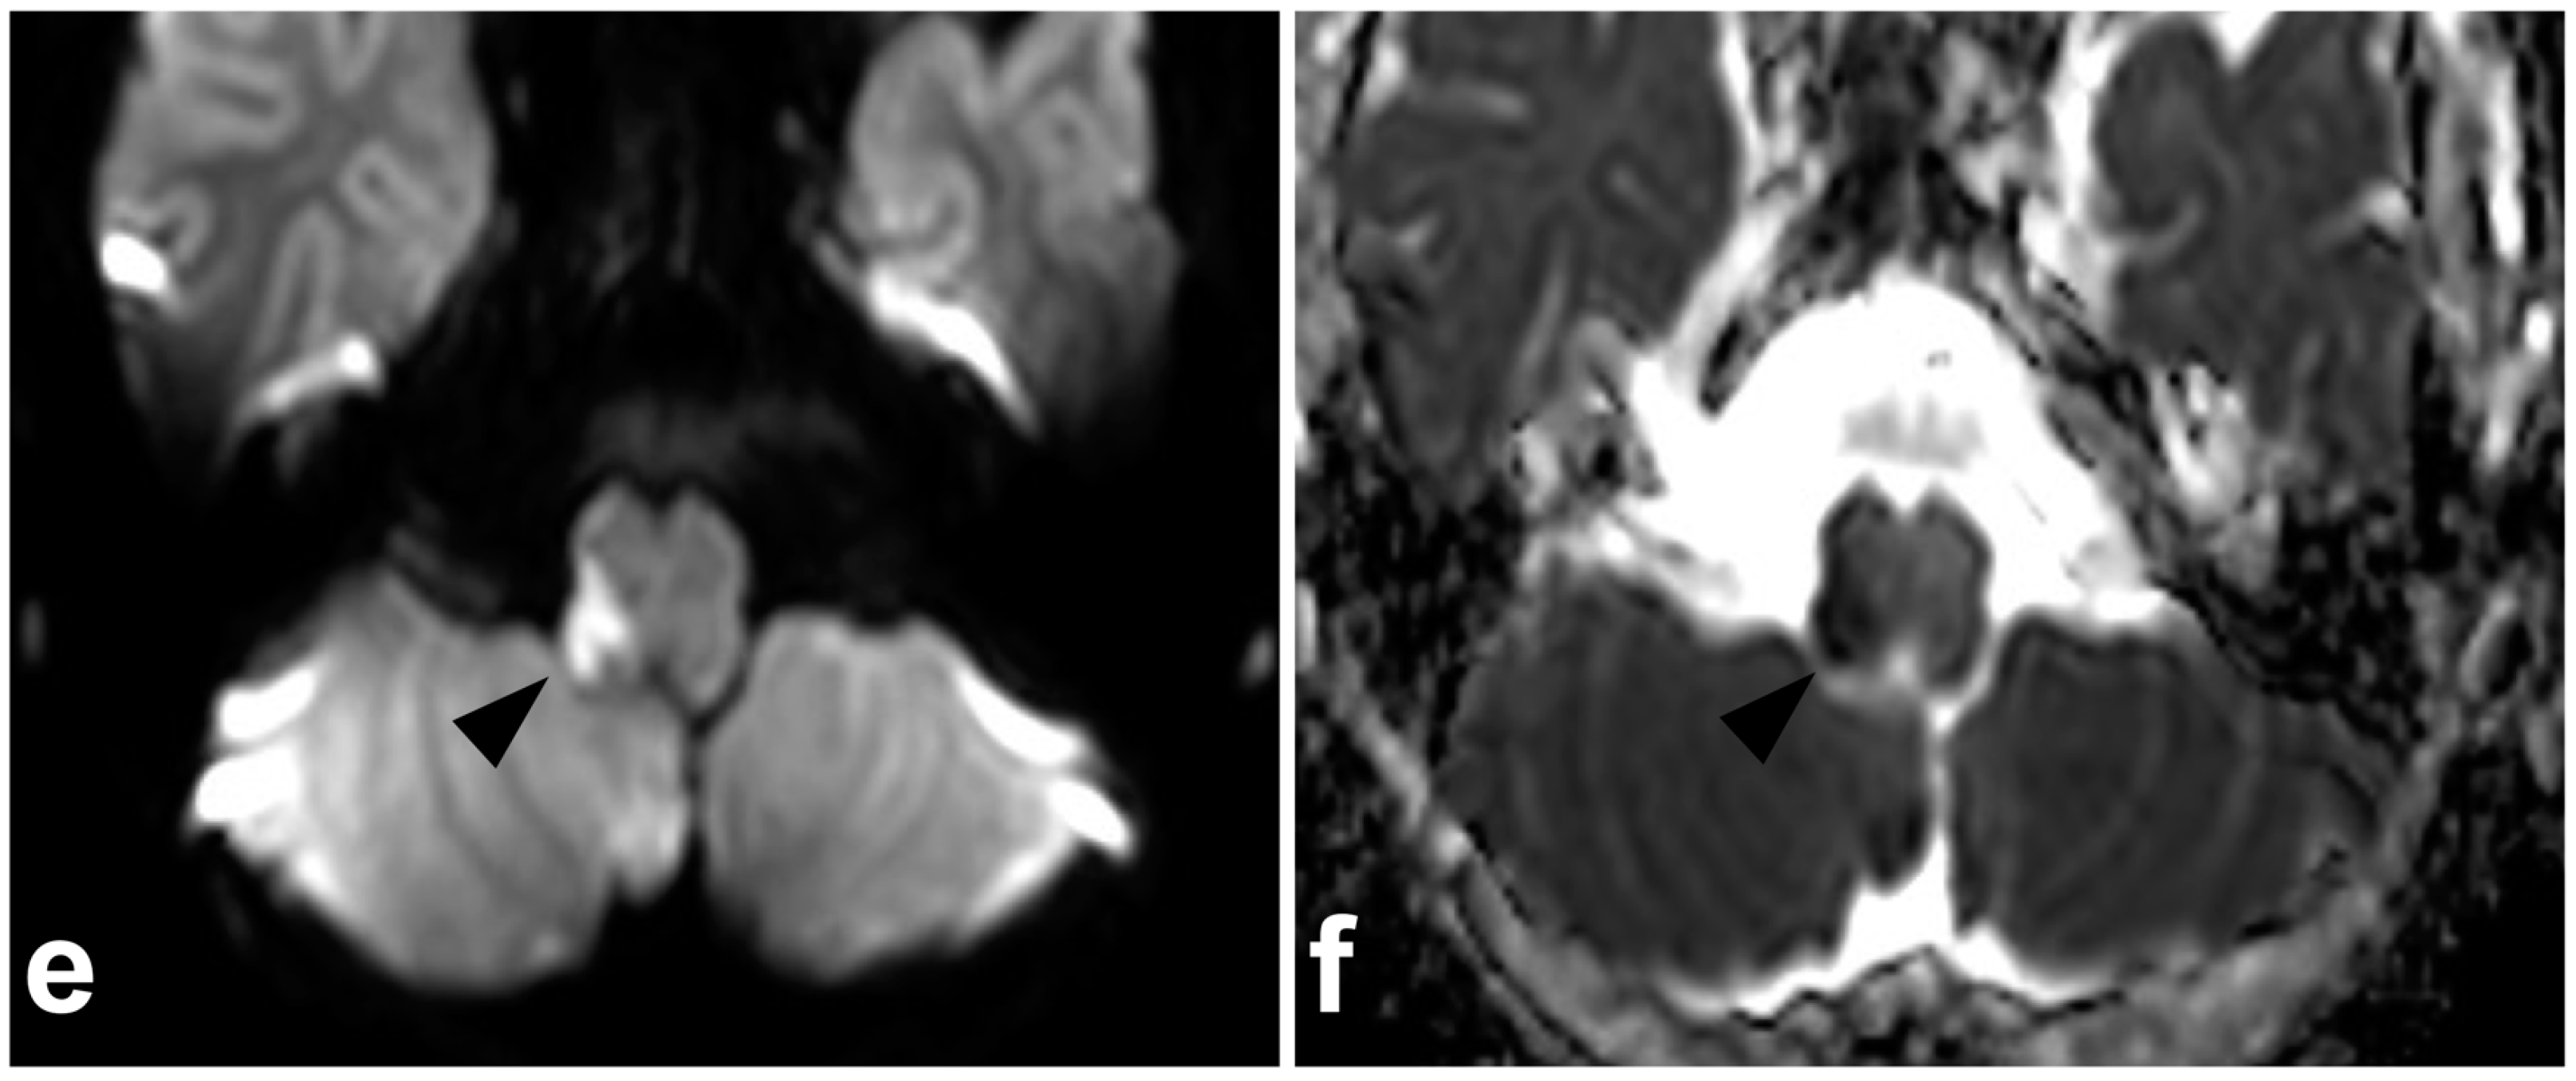

(a) Axial T2-weighted. (b) Axial plane of an isotropic fat-saturated T1-weighted (black blood sequence). (c) Right-sided off-midline sagittal STIR. (d) Left-sided off-midline sagittal STIR. (e) Axial trace diffusion-weighted image of the brain. (f) Axial apparent diffusion coefficient map of the brain. A 5-year-old male, found with impaired consciousness in unclear circumstances. MRI was performed to exclude trauma and revealed an occluding dissection of the right vertebral artery. The occluded right vertebral artery lacked a normal flow void on T2-weighted and STIR images (white arrows), while the patent left vertebral artery presents a normal flow void (white arrowhead). T1 fat-saturated sequence (b) reveals an intramural hematoma with a bright T1 signal in the wall of the dissected artery caudally to the completely occluded segment (curved arrow). Diffusion-weighted brain imaging demonstrates right-sided pontine infarction as a sequel to vertebral artery occlusion (black arrowheads). No other findings were suggestive of acute injury in the cervical spine or in the brain. The cause of the dissection remains unknown.

Figure 14.